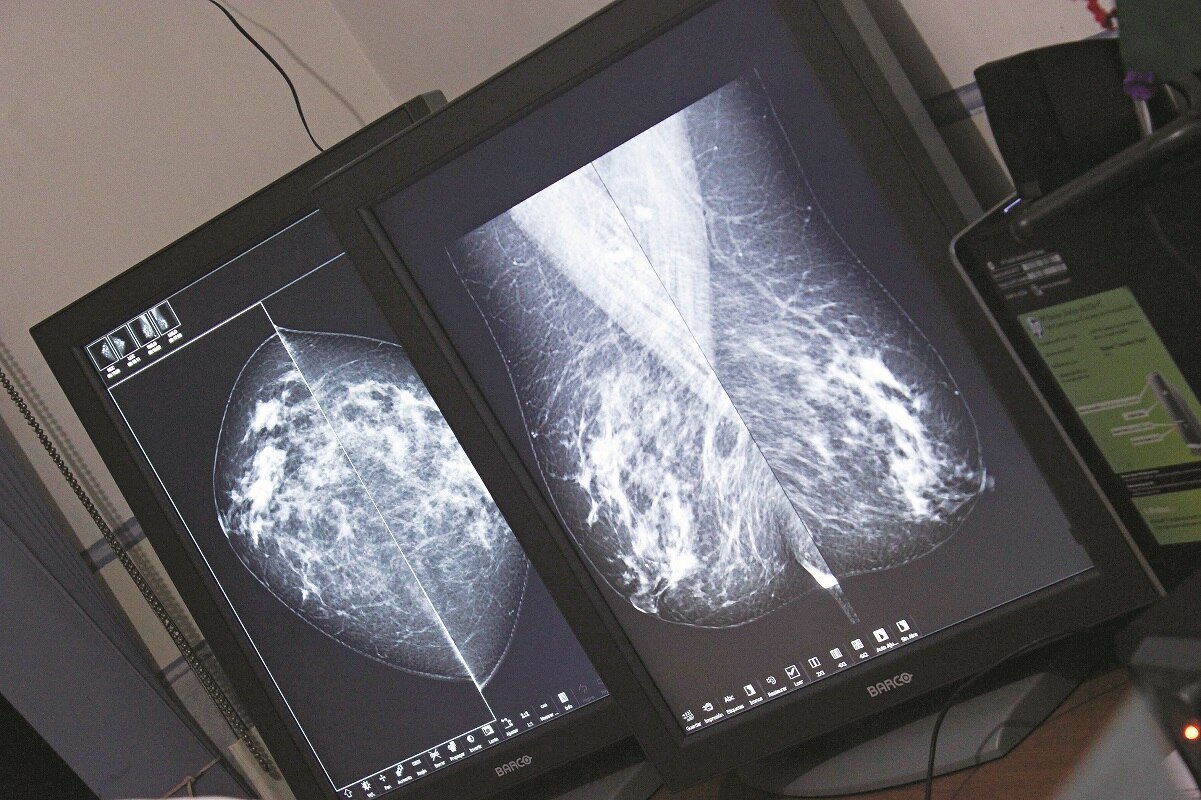

Sólo 15% de los casos de cáncer de mama se detectan a tiempo, de ahí que se convierte en la segunda causa de muerte de mujeres en el país, con un promedio de un fallecimiento cada dos horas, advirtió la doctora Jaquelina Aguillón Roa, responsable del programa Cáncer de la Mujer en la Secretaría de Salud de Querétaro.

Esa alta mortandad surge porque 85% de los casos no se detecta a tiempo, refirió.

El de mama, es un tipo de cáncer imposible de prevenir, lo único en lo que puede trabajarse es en detectarlo a tiempo, por lo que se requiere del apoyo de los organismos escolares y empresariales.